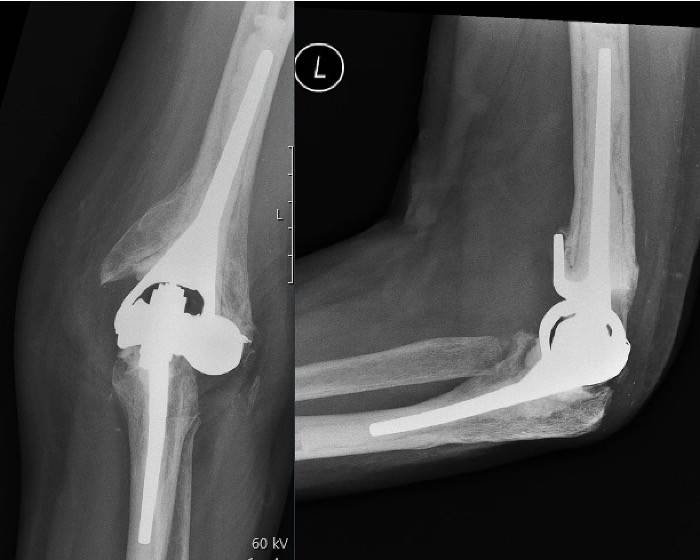

Elbow Replacement

Elbow replacement surgery, also known as total elbow arthroplasty (TEA), is a procedure in which the damaged parts of the elbow joint are replaced with artificial components (prosthesis). Though less common than hip or knee replacements, it can significantly reduce pain and improve function in patients with severe elbow joint damage.

- Total Elbow Arthroplasty (Linked Prosthesis)

- The humeral and ulnar components are connected (hinged) with a metal axle

- Provides stability

- Most common type, especially in cases with weak ligaments or bone